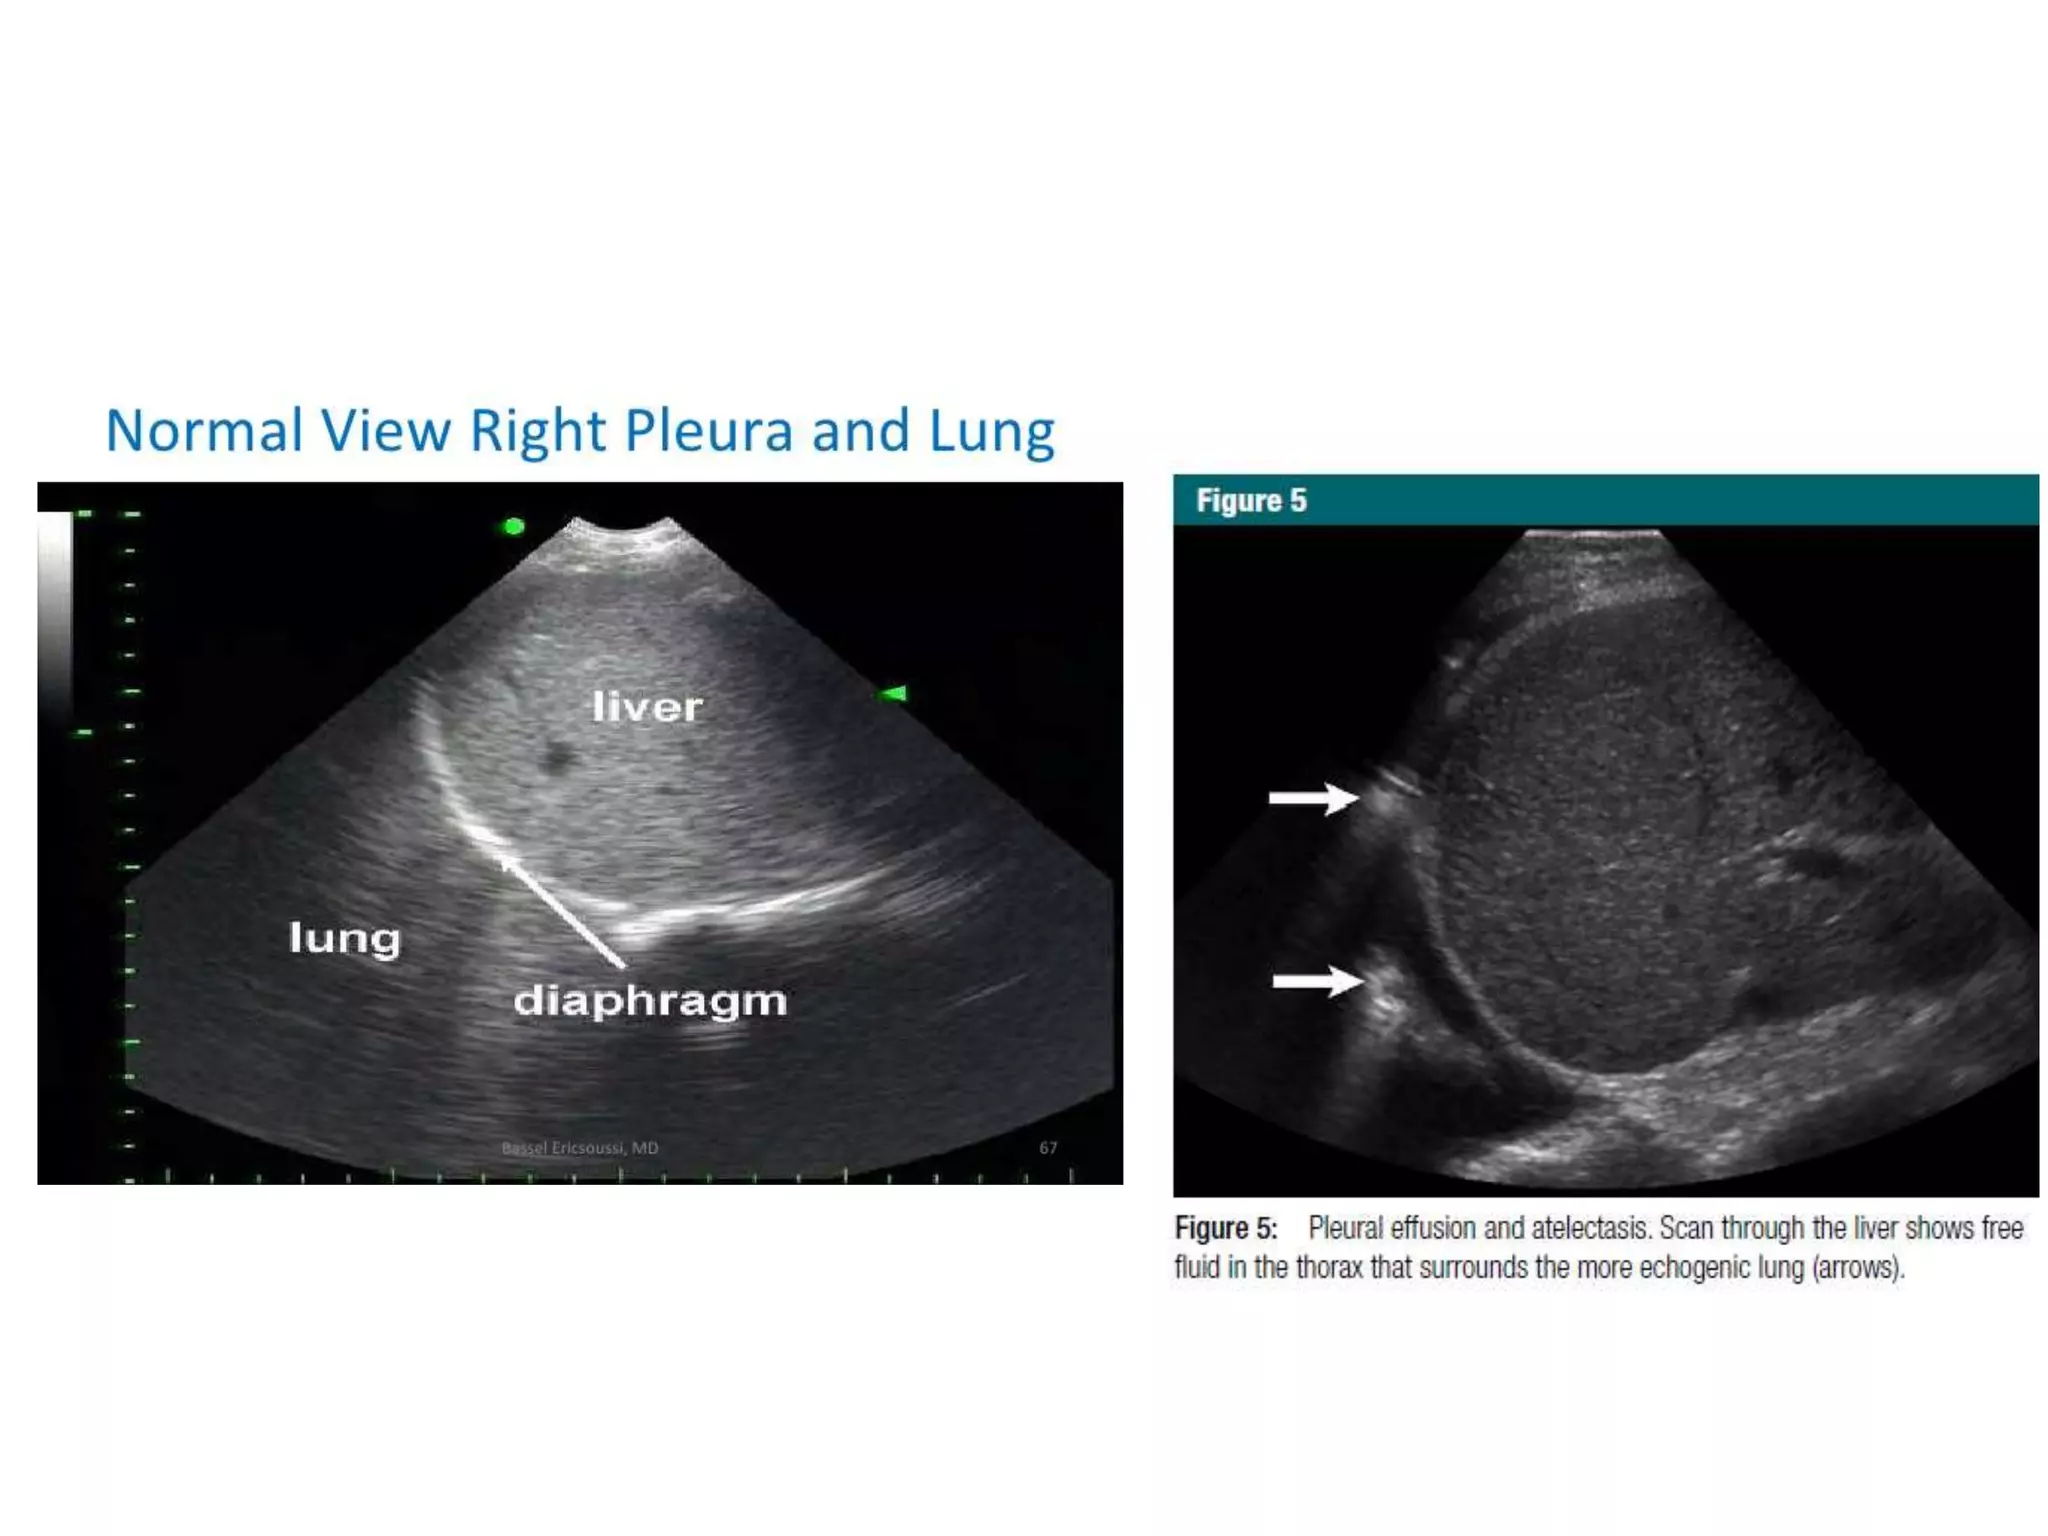

Hemothorax or Pleural Effusion

• The right pleural space  interface between the dome

of the liver and diaphragm

• echogenic curvilinear line, and echoes similar to liver

parenchyma

• Normal lung may intermittently distort this interface

during inspiration, referred to as the “curtain sign”

• anechoic or have mixed (hemorrhage, exudate,

transudate, empyema).

• Atelectatic lung can also be seen with this view

• Upright or reverse Trendelenburg positioning